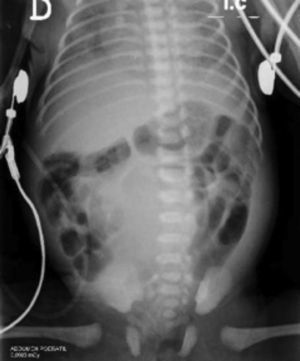

En el ecocardiograma se demostró comunicación interauricular (ostium secundum), conducto arterioso persistente e hipertensión pulmonar. La radiografía simple de abdomen evidenció una imagen radioopaca que ocupaba el mesogastrio y rechazaba las asas intestinales (fig. 2). Se sospechó una megavejiga, sin descartarse obstrucción de los uréteres y la uretra, por lo cual se practicó ecografía renal. En esta se informó ureterohidronefrosis con hidronefrosis izquierda de grado II y derecha de grado III, y aumento difuso de la ecogenicidad renal bilateral, posiblemente por insuficiencia renal crónica (fig. 3); además, se evidenció imagen de masa que ocupaba el mesogastrio y el hipogastrio, de aspecto quístico con partículas en su interior y con aparente comunicación con la vejiga. Se consideró que podía corresponder a un quiste del uraco, por lo que se sugirió practicar una cistouretrografíamiccional.